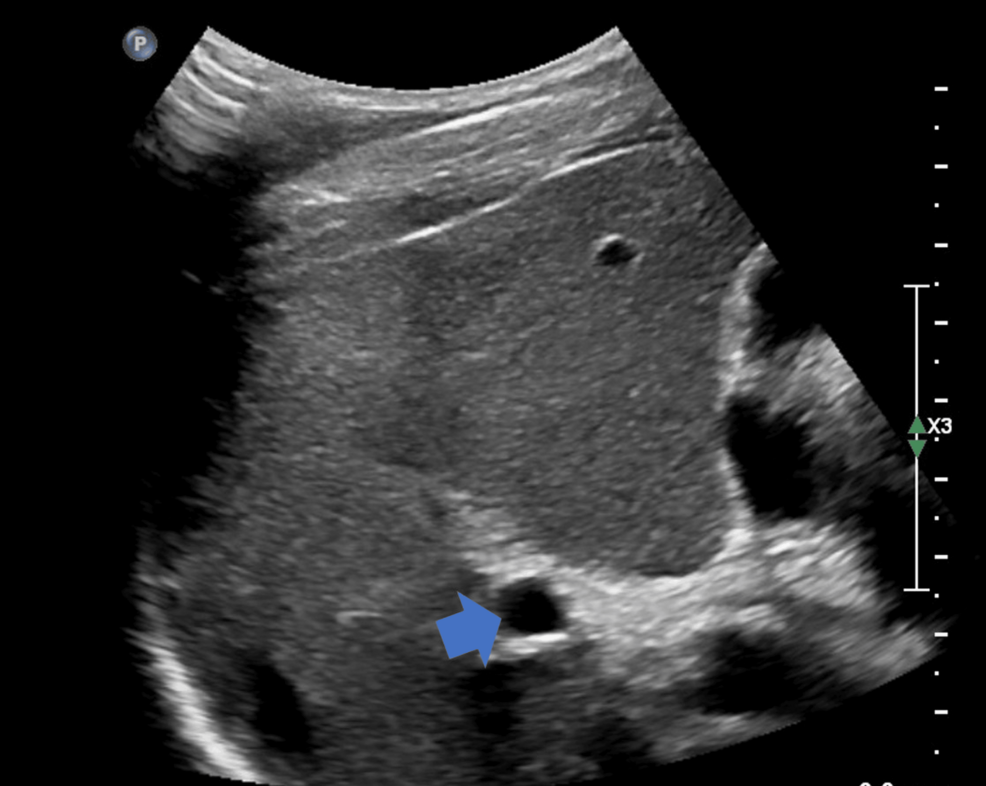

Liver trauma (Laceration)

Liver Trauma (Hematoma)